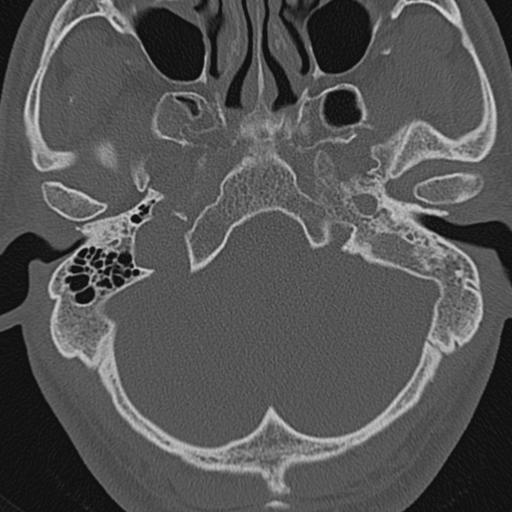

以下是引用zxl51642在2009-8-25 13:37:00的发言:[br]1、左侧慢性硬化型中耳乳突炎(中耳鼓室腔及听小骨受累),并胆脂瘤形成;2、左侧外耳道软组织密度影填塞,考虑炎性肉芽肿,建议结合临床;3、右侧颈静脉窝较左侧明显扩大,不排除颈静脉球瘤,建议mr进一步检查。

以下是引用随光逐影在2009-8-25 19:05:00的发言:[br]1)左侧慢性中耳乳突炎(肉芽肿或胆脂瘤形成),左侧外耳道炎性肉芽肿。2)右侧颈静脉球高位。